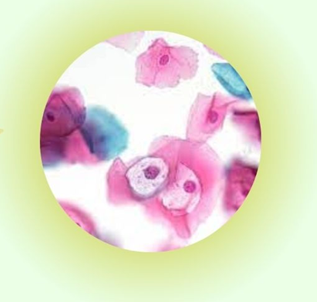

Infografía explicativa de la elaboración de un glosario de terminología científico-técnica sobre el aparato genital femenino y la mama.